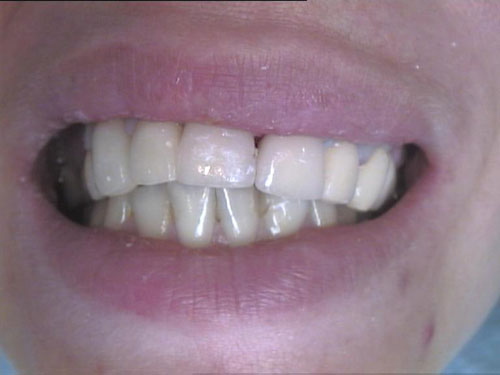

Zahnbleichen